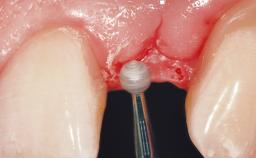

A 30-year-old female patient had lost tooth 21 and was referred to our clinic for consultation and treatment. Due to advanced apical infection, tooth 21 had been extracted two months earlier at another clinic and an acrylic-resin tooth had been bonded to the adjacent teeth. The patient desired implant treatment to avoid any damage to the adjacent natural teeth. While the patient had no history of any systemic disorder, she was a heavy smoker and exhibited medium to advanced periodontitis in the entire jaw. After the initial treatment to achieve a pocket probing depth of less than 4 mm and no bleeding on probing, a decrease in the height of the papillae mesial and distal to the extraction site and overall gingival recession were observed.

Bone Augmentation Horizontal|Staged

Augmentation Materials Autogenous chips|Membrane

Soft Tissue Grafting Simultaneous